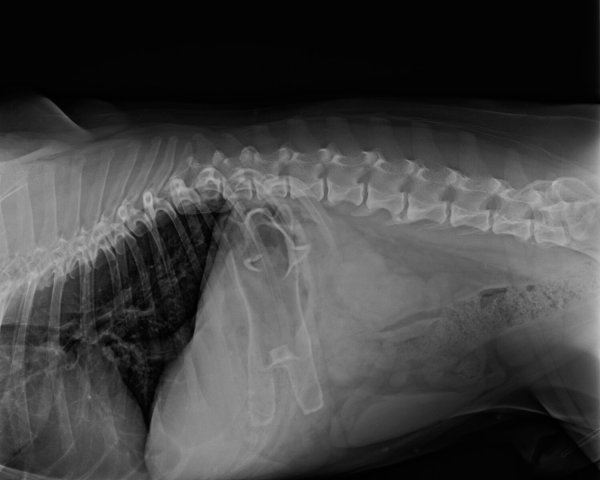

Die Umrisse des verschluckten Gegenstandes sind sehr gut zu erkennen. - © NW

Die Umrisse des verschluckten Gegenstandes sind sehr gut zu erkennen. (© NW)